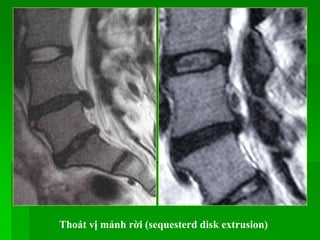

Thoát vị mảnh rời (sequesterd disk extrusion)

 Extrusion (with or without free fragment): Bờ của đĩa đệm nhô ra

< 50% của chu vi đĩa đệm bình thường và phần thoát vị có chiều rộng

< chiều cao.

Thoát vị mảnhrời (sequesterd disk extrusion)